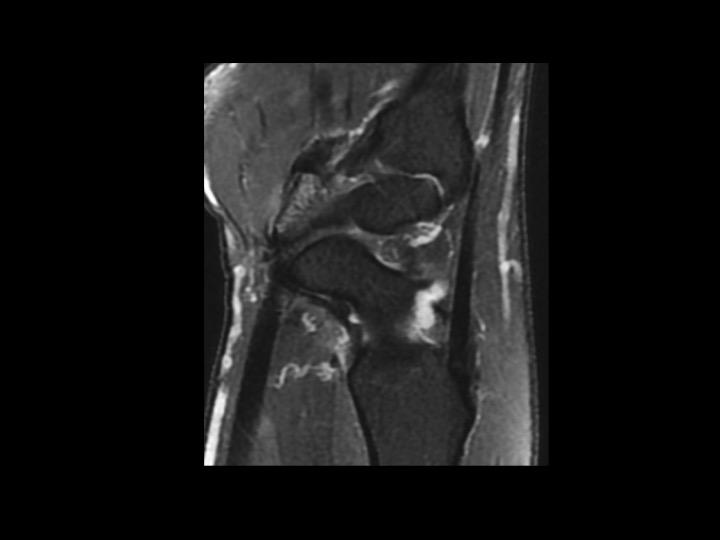

48F pain 2 weeks after fall

Keeping the theme of very subtle fractures. This fracture is easy to miss in the Cor and Sagittal plane unless you recognize the subtle marrow edema at the volar ridge. Cleary visible in the axial plane at the insertion of the transverse carpal retinaculum. These type II avulsions of the trapezium volar ridge may have a tendency toward non-union and may be a source of chronic pain.

trapezium ( RID2193 )